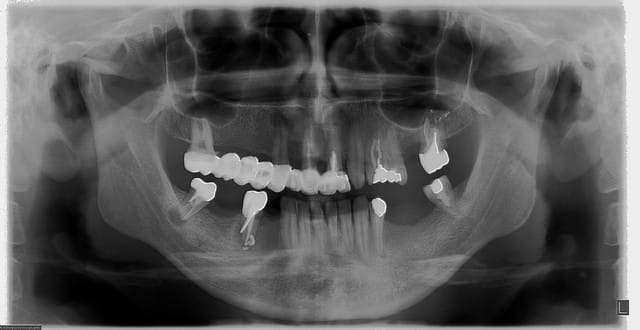

Si j'ai bien compris ce qu'insinuent certains d'entre vous, c'est qu'il est tout à fait normal de soigner les gens comme le patient ci-dessous, et que cela est même tout à fait justifié par les tarifs ridicule de notre bonne vieille nomenclature.

Si certains se contrebalancent de l’hygiène, de l’aseptise, et de la stérilisation, c'est pas grave non plus!

Il ne faut surtout rien dire, puisqu'on pourrait nous suspecter de manquer de confraternité, ou pire d'un pêché d'orgueil!

Après tout, tous ces soins mal fait seront autant de cas intéressant pour d'autres praticiens compétents, ou pas...

Bien sûre que personne ne peut prétendre tout savoir, bien sûre que personne n'est à l'abri d'une erreur, mais dans ce cas là il s'agit simplement d'un aléa thérapeutique... Mais lorsque les erreurs deviennent systématiques, lorsqu'elles ne sont pas reconnues, et que les patients soufrant et demandant des explications ne reçoivent qu'une ordonnance d'antalgique et un "tout va bien ne vous inquiétez pas!"

Errare humanum est, perseverare diabolicum!

Si en plus les erreurs sont faites de manière intentionnelle parce les soins sont mal remboursés... C'est certainement pas comme cela que l'on va réussir à redorer notre blason! Car c'est de cela dont il s'agit, petit à petit on passera non seulement pour des nantis, des cupides, mais aussi pour des escrocs, des incompétents, voir même des criminels!